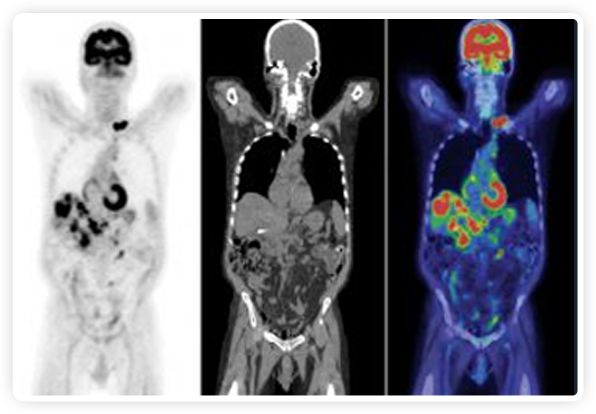

提起放療設備的引導系統,大家通常會想到結構性成像的CT或核磁。但你有沒有想過用功能性成像來引導放療呢?美國的一家醫(yī)療器械公司從2011年就致力于研究開發(fā)用PET提供生物學指導放射治療的設備BgRT。BgRT能實時利用癌癥的生物學特征作為信號指導治療全身腫瘤。

RefleXion將PET成像與立體定向放射治療相結合。在注射示蹤劑后,RefleXion的技術基于示蹤劑信號實時地在一個或多個目標上引導治療性X射線。使用這種專有方法,RefleXion的平臺有可能比現有系統向癌癥病變提供更高劑量的輻射,并改善周圍健康組織的保護。

為了避免PET長圖像采集時間,RefleXion開發(fā)了一項專利技術使用重合的PET光子對來指導放射治療束,因為實時檢測發(fā)射的光子,為生物指導提供了一種時間有效的方法。